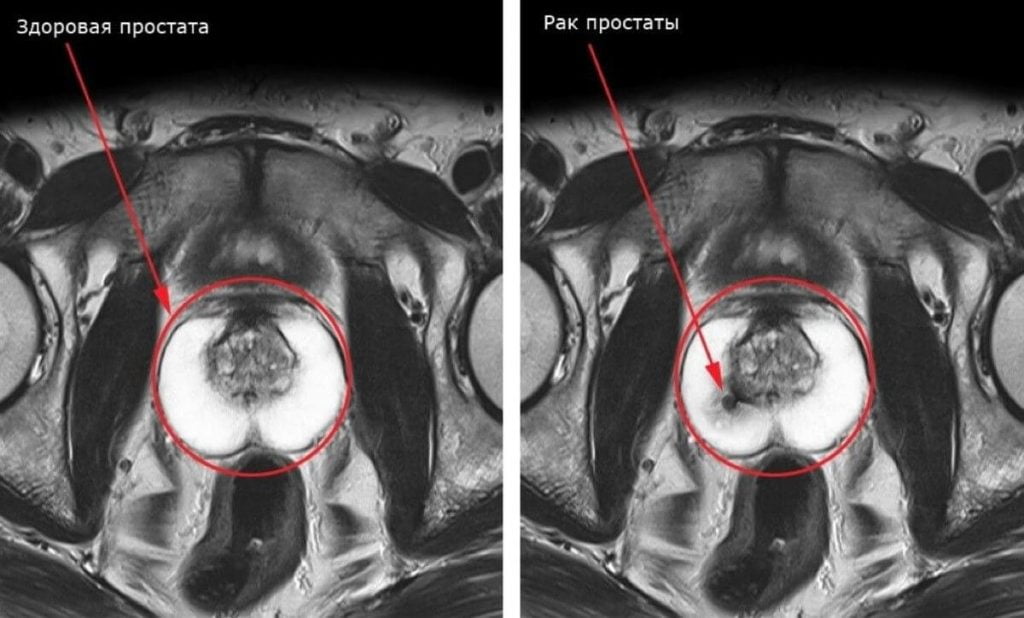

A prostatite em si é uma rota direta para o adenôma da próstata e, em seguida, para a impotência e o câncer. Ainda quando não são observados sintomas, a prostatite já pode estar presente, interferindo negativamente nas atividades intimas dos homens, mesmo quando jovens.